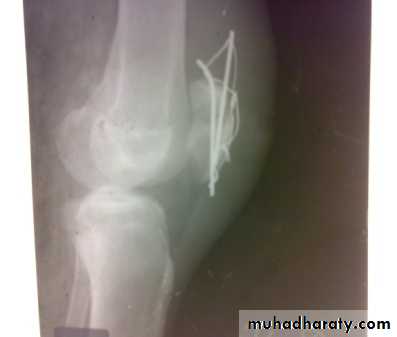

Supracondylar fracture with its fixation by L – plate and screws

dynamic condylar screw and plate

In old internal fixation is often preferable and the patient can get out of bed sooner (dynamic condylar screw and plate) .